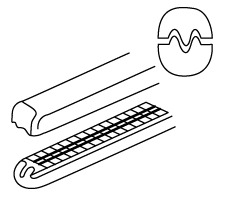

Surgical forceps may be broadly divided into two categories, thumb forceps (frequently called surgical or medical tweezers, gripping forceps, non-locking forceps or pinning forceps) and ring forceps (also called hemostats, hemostatic forceps and locking forceps). Thumb forceps are spring forceps used by compression between your thumb and forefinger and are used for grasping, holding or manipulating body tissue. They are non-ratchet style. For example, you could use thumb forceps to hold or move tissue during surgery or to move dressings. Hemostatic forceps are hinged forceps that look more like scissors. Hinged forceps may come with or without a "lock" for clamping. Thumb forceps are available with a variety of tips. The tips may be flat, serrated, cupped, ringed, grooved, diamond dusted or have teeth. The tips may also be straight, curved or angled. See the images below. Serrated tweezers (thumb forceps) are designed for use with tissues. The serrations or teeth actually cause less damage than flat forceps, because it requires less pressure to maintain a firm grip. Use smooth or cross-hatched forceps for removing sutures, moving dressing or other drapes. Thumb forceps can be broadly grouped as tissue forceps and dressing forceps. Commonly used thumb forceps include Adson forceps, Iris forceps and Foester forceps.

Surgical forceps may be broadly divided into two categories, thumb forceps (frequently called surgical or medical tweezers, gripping forceps, non-locking forceps or pinning forceps) and ring forceps (also called hemostats, hemostatic forceps and locking forceps). Thumb forceps are spring forceps used by compression between your thumb and forefinger and are used for grasping, holding or manipulating body tissue. They are non-ratchet style. For example, you could use thumb forceps to hold or move tissue during surgery or to move dressings. Hemostatic forceps are hinged forceps that look more like scissors. Hinged forceps may come with or without a "lock" for clamping. Thumb forceps are available with a variety of tips. The tips may be flat, serrated, cupped, ringed, grooved, diamond dusted or have teeth. The tips may also be straight, curved or angled. See the images below. Serrated tweezers (thumb forceps) are designed for use with tissues. The serrations or teeth actually cause less damage than flat forceps, because it requires less pressure to maintain a firm grip. Use smooth or cross-hatched forceps for removing sutures, moving dressing or other drapes. Thumb forceps can be broadly grouped as tissue forceps and dressing forceps. Commonly used thumb forceps include Adson forceps, Iris forceps and Foester forceps.

Locking forceps may be called clamps and are used to securely hold tissue. When they are used to control blood flow, they are called hemostats. When used to grasp and manipulate needles, they are called needle holders.